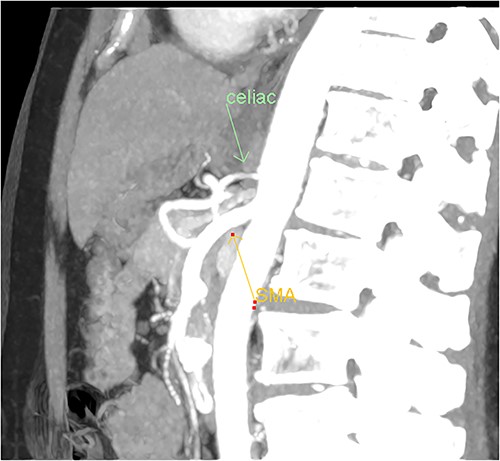

A multiphase CT of the pancreas had unexpected findings. There were no pancreatic masses on the arterial and portal phase study, and no paraaortic or mesenteric lymphadenopathy. The abnormal calcification seen on the previous study corresponded to a dilated vessel along the superior margin of the pancreatic body. This dilated vessel was an abnormal communication between a tortuous ecstatic gastroduodenal artery and the first branch of the SMA, a Buhler’s arc communication. The celiac axis origin was narrowed >90%. No other suspicious solid organ mass lesion was identified. Soft tissues were unremarkable (Figs 5–8).

Multiphase CT pancreas, sagittal view: abnormal communication between the CA and the SMA. The celiac axis is markedly narrowed, >90%.